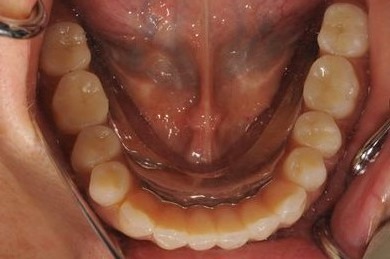

インプラントの症例写真 IMPLANT

インプラント治療+オーバーデンチャー

| 治療方針 | 下顎に2本インプラントを埋入し、アタッチメントをつけて、オーバーデンチャーを装着し、はずれにくく、安定した義歯を装着する。 | ||||||||||||||||||||||||||||||||

| 治療内容 | インプラント2本(テンポラリーインプラント)、アタッチメント、コバルトクロム床オーバーデンチャー | ||||||||||||||||||||||||||||||||

| 総治療費 | 1,540,350円 | ||||||||||||||||||||||||||||||||

| 治療期間 | 5ヶ月 |